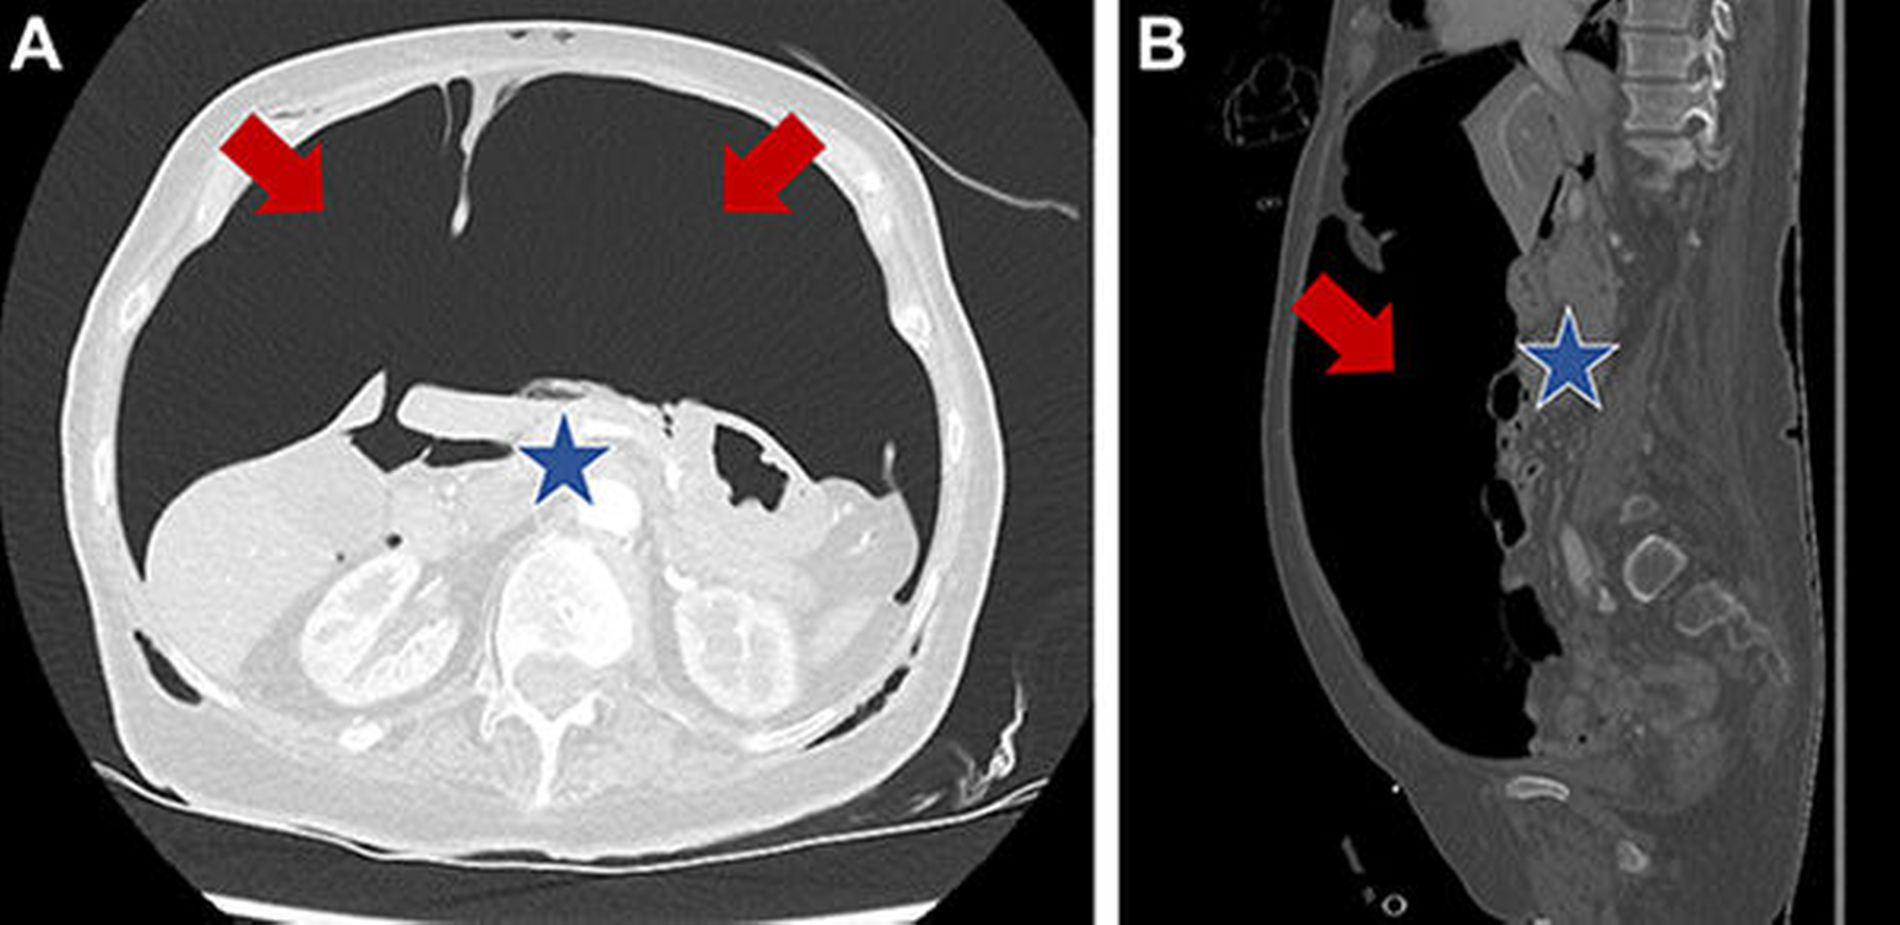

Der Spannungspneumothorax wurde akut per Nadeldekompressionen und dann über Thoraxdrainagen beidseits entlastet. In der anschließend durchgeführten CT-Untersuchung von Thorax und Abdomen zeigte sich neben dem beidseitigen, entlasteten Mantelpneumothorax zusätzlich ein Pneumomediastinum mit Luftansammlungen im oberen, ventralen und dorsalen Mediastinum (Abbildung 2), zusätzlich dazu eine Ansammlung von freier Luft im Abdomen (Abbildung 3).

In der daraufhin durchgeführten diagnostischen Laparoskopie konnten neben einer Perforation des Diaphragmas links keine weiteren Organperforationen bzw. -lazerationen festgestellt werden. Die Patientin wurde im Anschluss auf die Intensivstation verlegt und konnte 24 Stunden später in stabilem Allgemeinzustand wieder auf die Normalstation verlegt werden.